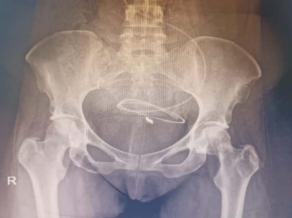

31 year old female presented to us with complaints of limp while walking from past few months. No history of fever, loss of appetite, weight loss or any other constitutional symptoms. Patient is a post operated case of Medulloblastoma brain and occipital craniotomy with VP shunting was done in May 2018 in London for the same along with adjuvant chemo-radiation. Patient received craniospinal radiotherapy (35Gy/21fractions) + (20Gy/12 fractions) for approx. 6 weeks in Aug-Sep 2018. Patient received 6 cycles of Cisplatin, Vincristine and Lomustine, during Sep 2018-Dec 2018. Patient was on regular follow up and regular MRI Brain was done during follow up and patient was asymptomatic during the time period of last 4 years, until last month when she developed sudden onset right lower limb limp while walking. Patient was evaluated for above mentioned complaints and relevant scans were done. On X ray (Fig. 1),   MRI (Fig. 2) and PET scan (Fig. 3) multiple lytic lesion were seen involving D7 vertebra, right ischium and left proximal femur. Left proximal femur lesion was measuring 5.5 x 3.8 x 3.2 cm with a cortical breach. CT guided biopsy from D7 vertebra was done which showed typical emperipolesis (Fig. 4) S/O Rosai Dorfman Disease. IHC was done and was positive for S100 and CD68 suggestive and negative for CD1a suggestive of Rosai Dorfman Disease. High risk of pathological fracture of left proximal femur (Mirel’s Score – 11) was explained to the patient and cemented bipolar hemiarthroplasty was done for left hip. Post op patient was mobilized on Day 1 and dressing was changed at Day 5 and patient was discharged at Day 6. Final histopathology impression was s/o Extranodal Rosai Dorfman disease.

Fig. 1(a) Pre op X ray                                   (b) Post op X ray